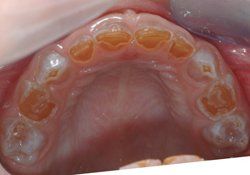

Milchgebiss eines 5-jährigen Kindes mit Dentinogenesis imperfecta. Die Zahnkronen sind bereits stark abgenutzt und typisch bernsteinfarben.

Betroffen sind immer alle Zähne sowohl im Milchgebiss als auch im bleibenden Gebiss. Typischerweise haben die Milchzähne eine bernsteinartige Farbe während die bleibenden Zähne eher gräulich erscheinen. Durch das mindermineralisierte Dentin kommt es bei Kaubelastung schnell zu großflächigen Abplatzungen des Zahnschmelzes. Das weiche Dentin unterliegt dann einer raschen Abrasion (Abnutzung) und die Zahnkrone wirkt schon nach kurzer Zeit stark abgeschliffen.